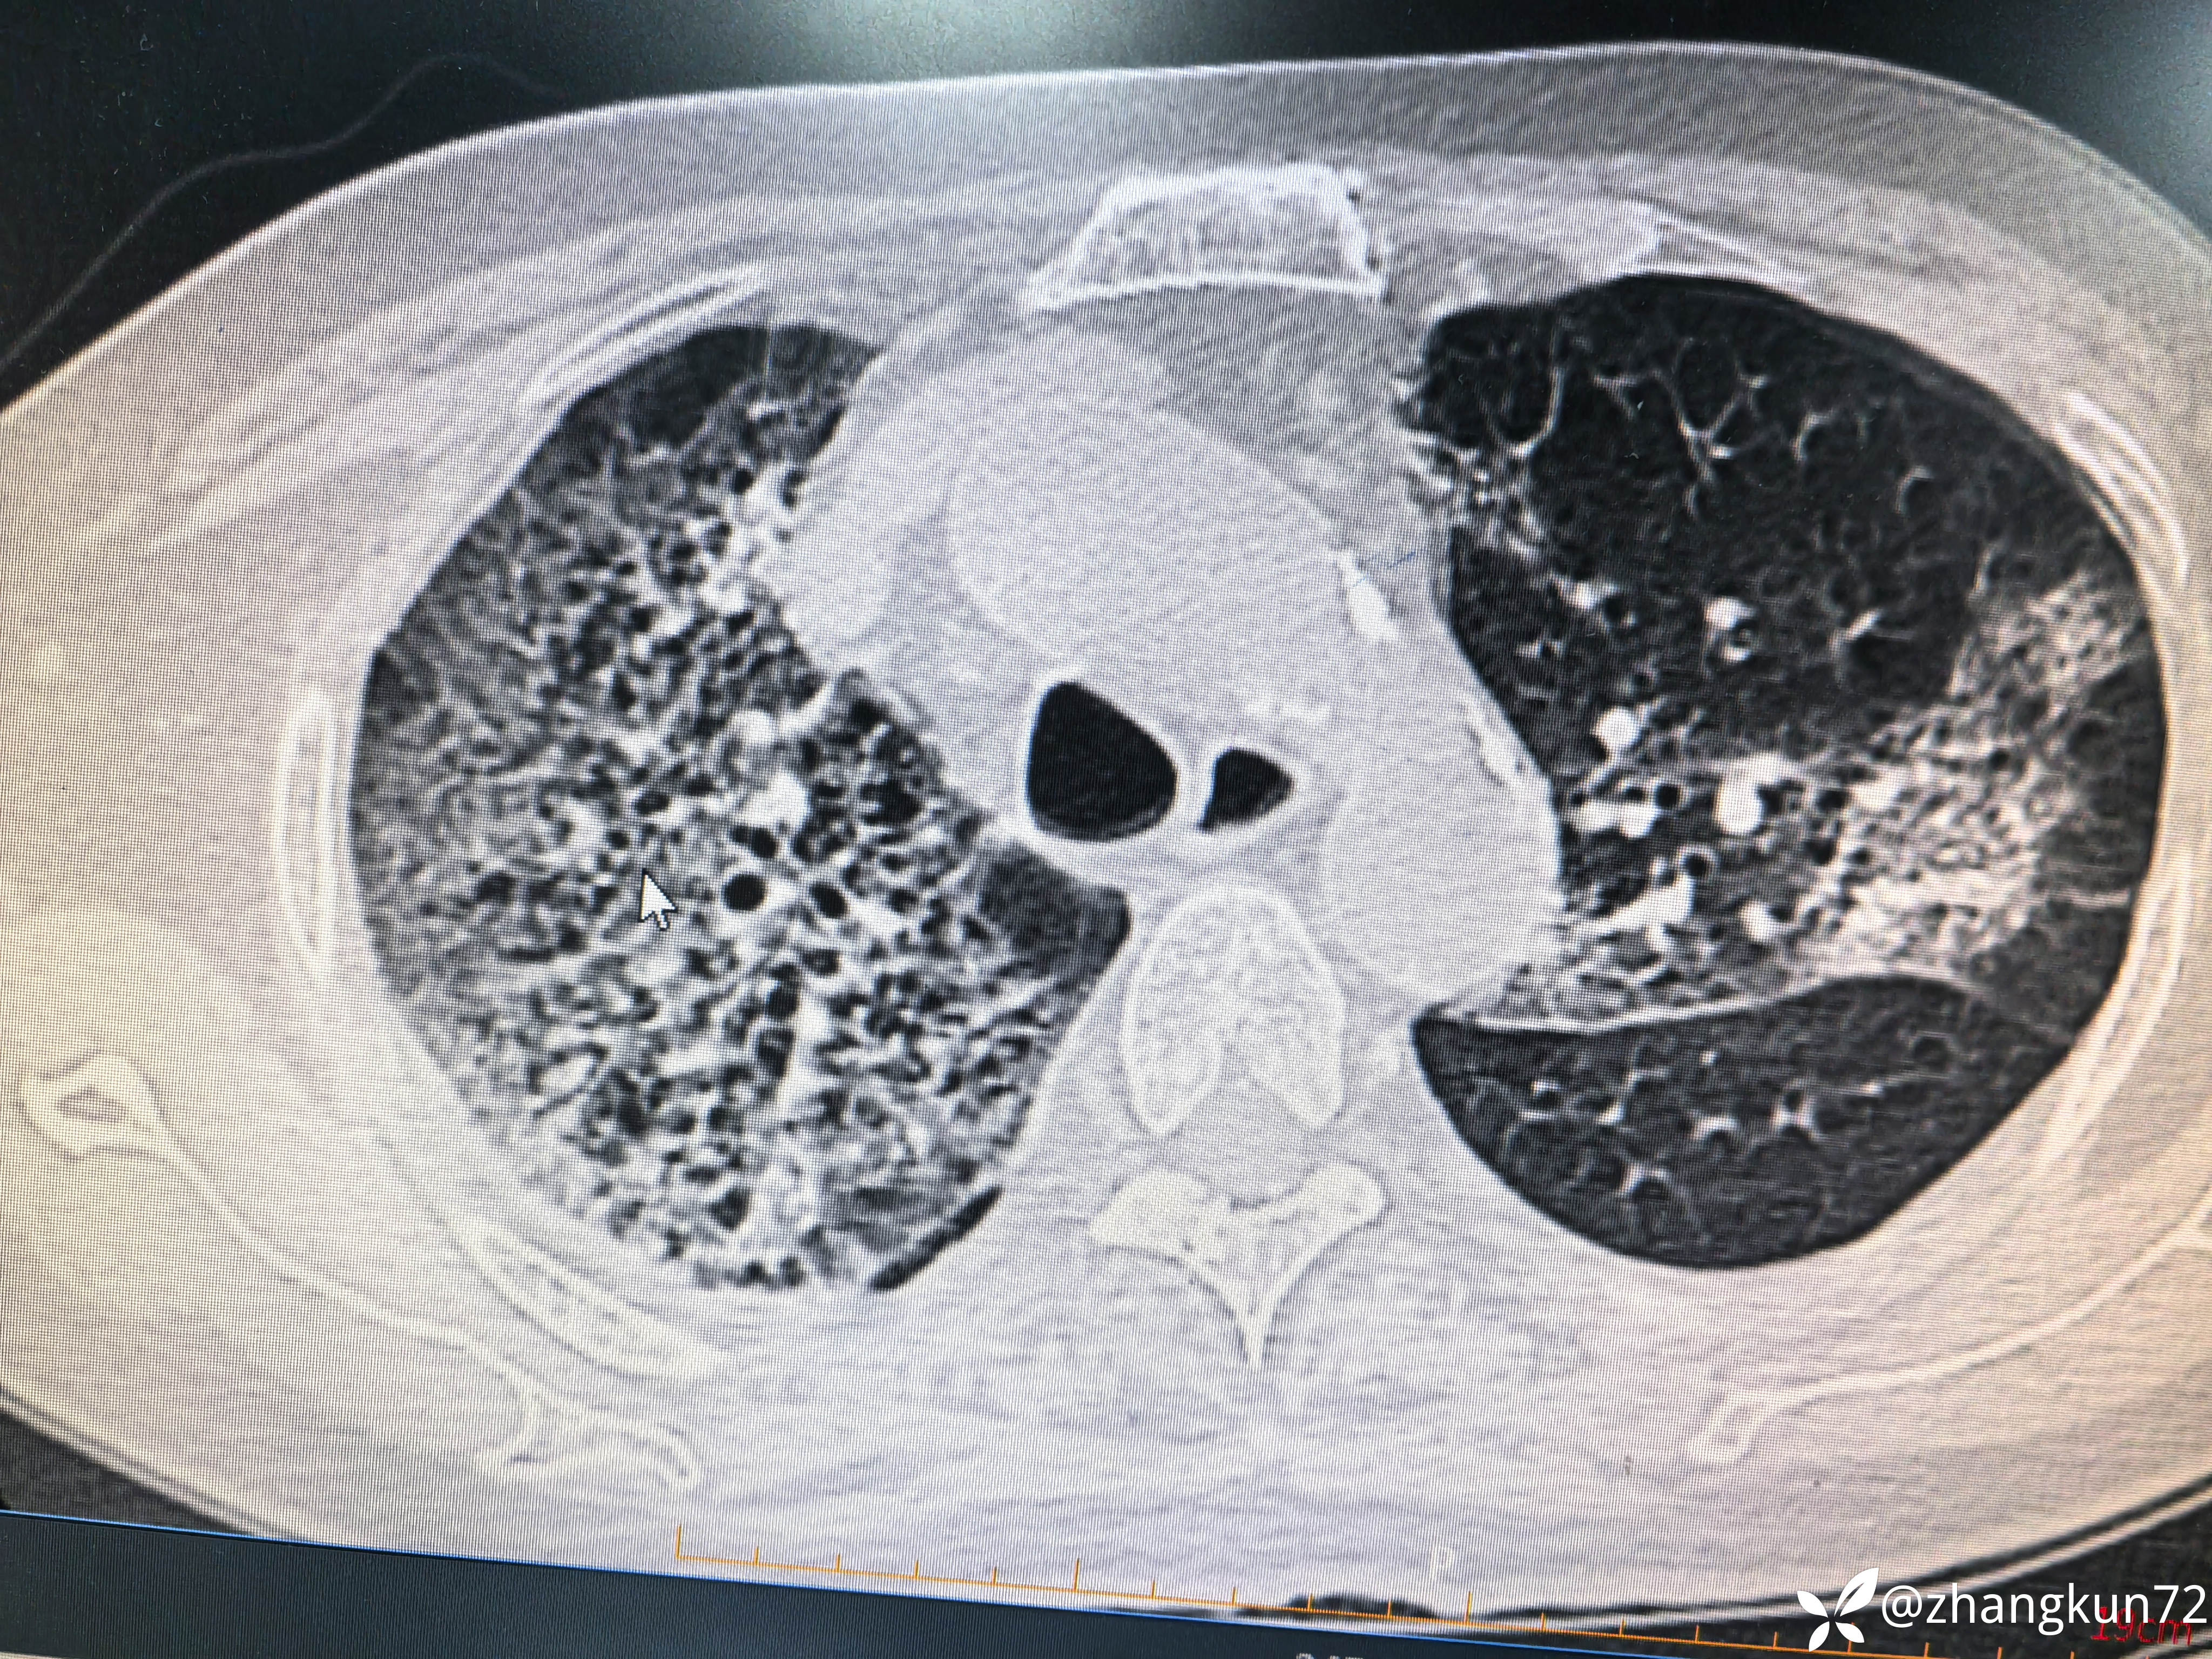

异常胸部ct

【检查】:白细胞计数正常,超敏c反应蛋白6.41,降钙素原0.09,白介素6 9.04,真菌G试验阴性,GM试验1.13,新冠核酸阴性,甲流阴性,乙流阴性,支原体抗体阴性,梅毒及艾滋病等病原体阴性,痰培养一次检查肺炎克雷伯杆菌。

【临床诊断】:1型呼吸衰竭,肺部感染,肾上腺皮质功能减退证,甲状腺功能减退症

目前治疗一般,是否为感染,什么病原体感染